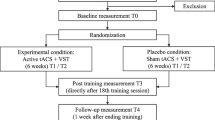

Visual stimuli

To test the subject’s function of visuospatial attention, we chose a line bisection judgment task. We adapted the “landmark task” originally used in patients to measure the perceptual component of neglect (Harvey et al. 1995). Visual stimuli were designed as white background-pictures with black horizontal lines bisected by a black vertical landmark (Fig. 1). The vertical transection bar (height 29 mm, width 1 mm) was positioned middle-centered on the screen and to the subject’s midline. The horizontal - left and right - line segments (width 1 mm) varied in length from 31 mm to 150 mm. Our task set consisted of 72 different pictures. In 24 pictures the line was bisected symmetrically with an equal length of the left and right segment, and in 48 pictures the line was bisected asymmetrically, to the right (with a longer left segment) or rather left (with a longer right segment). As described in previous studies, we decided to present the task pictures tachistoscopically with a display time of 50 ms (Fierro 2000; Salatino et al. 2014). The inter-picture-interval (IPI) was set to 3000 ms; two consecutive pictures were therefore separated by a black screen for 2950 ms. The order of pictures was randomized. On each picture the subject was asked to report whether the presented line appeared to be longer left, longer right, or equal in length by naming the appropriate selection orally (Fierro 2000). To familiarize subject and task setting, we conducted a baseline session before rTMS stimulation (Lioumis et al. 2012; Sollmann et al. 2015c). Baseline conditions equaled the outlined mapping conditions; baseline performance was recorded on video. We discarded all wrongly or hesitantly named pictures. In all cases, these were the first pictures presented; due to the short display time of 50 ms subjects needed to accommodate to situation and task set-up. We then made up a personalized task set for each volunteer for the following mapping.

Stimulation points and mapping procedure

Our mapping template contained 52 cortical spots per hemisphere, distributed to brain areas by use of the cortical parcellation system (CPS; Fig. 2, Table 1) (Corina et al. 2005). As reported recently, some brain regions could not be stimulated because stimulation is known to trigger unacceptable pain, i.e., the orbital part of the inferior frontal gyrus (orIFG), polar and anterior frontal regions (polFG, aSFG, aMFG), the polar temporal gyri (polTG) and the anterior middle temporal gyrus (aMTG). The inferior temporal gyrus (ITG) was not stimulated because stimulation is known not to trigger comparable effects due to increased distance to the skull and decreased stimulation intensity in the brain (Hauck et al. 2015a; Krieg et al. 2013). We anatomically identified the spots within both hemispheres in each subject’s 3-D MRI reconstruction and tagged them as stimulation points prior to each volunteer’s mapping. First, the baseline session was performed as mentioned above, then the mapping session was conducted as follows: Each hemisphere was stimulated twice, taking it in turns and starting with the left hemisphere; each stimulation point was stimulated 5 times, thus 10 times in total. For a maximal field induction the stimulation coil was placed tangentially to the skull in anterior-posterior field orientation (Epstein 1996; Lioumis et al. 2012; Miranda 2013).

RTMS data analysis

rTMS data were analyzed in a two-step process (Ille et al. 2015; Lioumis et al. 2012). At first, we evaluated the video-recorded task performance blinded to stimulation sites. Each response was linked with the subject’s baseline response to the respective Picture. Errors were categorized as follows:

We determined a mean RMT of 34.9 ± 8.9 % maximal stimulator output for the left hemisphere and of 34.5 ± 8.2 % for the right hemisphere (p = 0.9274; Table 2). Due to reported pain, we reduced the stimulation intensity after RMT determination in two cases (marked with an asterisk). Yet, the electric field strength on cortical level was higher than 55 V/m at all times and we did not observe any effect on error occurrence or frequency in these subjects compared to the whole collective as observed previously (Picht et al. 2013). All subjects tolerated the mapping well; mean discomfort was comparable for both hemispheres. During baseline testing 94.3 ± 4.1 % of the pictures were answered correctly, and the individual mapping task set consisted of 68 pictures on average. The number of baseline errors did not correlate with the number of errors during mapping conditions.